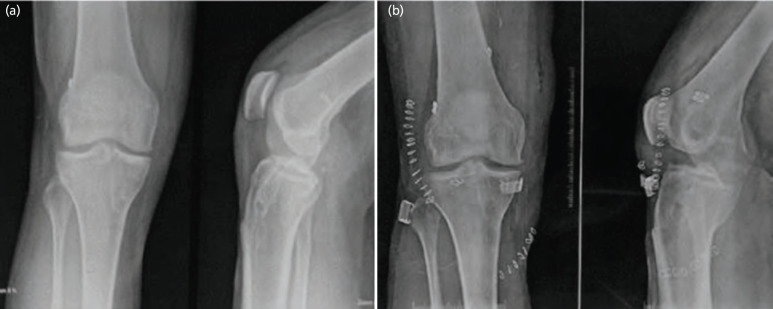

Introduction: The purpose of this study is to assess the outcomes of patients that underwent single-stage revision ACL reconstruction (ACLR) with peroneus longus tendon (PLT), augmented with lateral extra-articular tenodesis (LET) using the modified Lemaire technique.

Material and methods: All the 18 patients underwent arthroscopic single-stage revision ACLR using autologous PLT with an additional modified Limier LET procedure. Patients were thoroughly assessed pre- and post-operatively by the Lachman test, the pivot shift test, and the side-to-side difference by the Rolimeter. Functional evaluation was done with the help of the Lysholm score, the IKDC subjective score, Tegner score, VAS score, MARX activity rating scale and The American Orthopaedic Foot and Ankle Society (AOFAS) score. Post-operatively, patient satisfaction, return to sport, and physical activity were also recorded. SPSS ver. 22.0 software was used. Wilcoxon test, paired and unpaired t-tests were used to compare variables. Statistical significance was determined by a two-sided p-value <0.05.

Results: Regarding subjective evaluations; post-operative residual laxity, and return to sport and physical activity, all of the patients demonstrated excellent results. Post-operatively, there was significant improvement in the anterior knee laxity. According to the Marx Activity Rating Scale, the extent of sports engagement was significantly increased at 18 months following surgery (p<0.001). According to the AOFAS score (p=0.38), there were no documented significant donor site morbidities.

Conclusion: Single-stage revision ACLR using PLT with an additional modified Lemaire LET procedure results in a significant reduction in residual knee laxity with good clinical outcomes and a high return to play and physical activity.